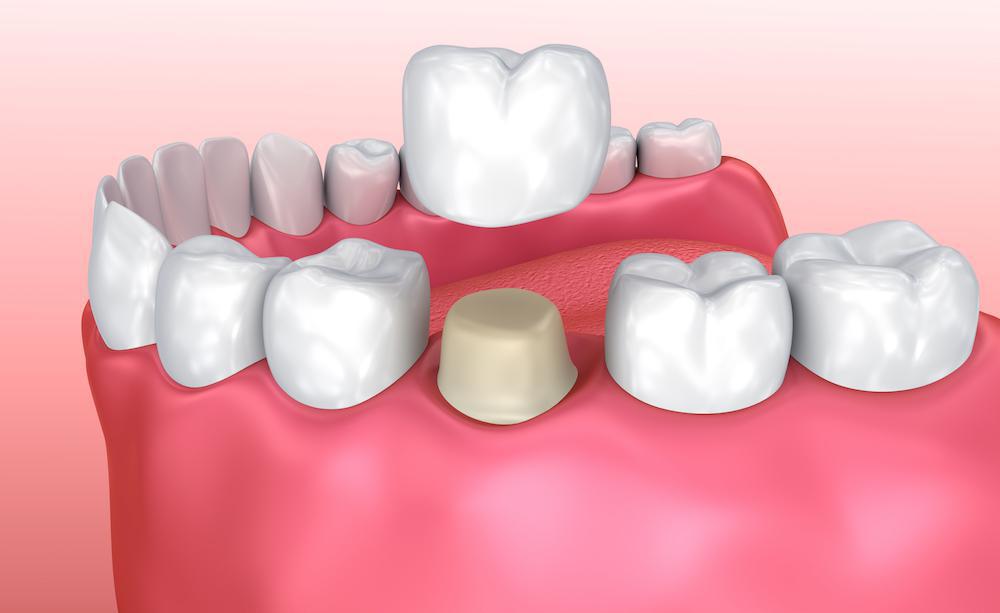

الحشوات غير المباشرة

الحشوات غير المباشرة تشبه الحشوات المركبة أو بلون السن باستثناء أنها مصنوعة في مختبر الأسنان وتتطلب زيارتين قبل وضعها وتؤخذ الحشوات غير المباشرة عندما لا يبقى ما يكفي من بنية الأسنان لدعم الحشوة ولكن لا يتضرر السن بشدة لدرجة أنه يحتاج إلى تاج.

خلال الزيارة الأولى يتم إزالة التسوس أو حشوة قديمة ثم أخذ طبعة لتسجيل شكل السن الذي يتم إصلاحه والأسنان المحيطة به ويتم إرسال الطبعة إلى مختبر طب الأسنان الذي يقوم بالحشو غير المباشر حيث يتم وضع حشوة مؤقتة لحماية السن أثناء إجراء عملية الترميم، وخلال الزيارة الثانية تتم إزالة الحشوة المؤقتة وسيتحقق طبيب الأسنان من مدى ملائمة الترميم.

هناك نوعان من الحشوات غير المباشرة: الحشوات المرصعة والداخلية.

- تطعيمات مماثلة لحشوات

- Onlays هي أكثر شمولاً من التطعيم

فهما أكثر دواماً وتستمر لفترة أطول بكثير من الحشوات التقليدية حيث تصل إلى 30 عاماً ويمكن أن تكون مصنوعة من الراتنج المركب بلون الأسنان والخزف أو الذهب كما أنها تضعف بنية الأسنان ولكن تفعل ذلك بدرجة أقل بكثير من الحشوات التقليدية.